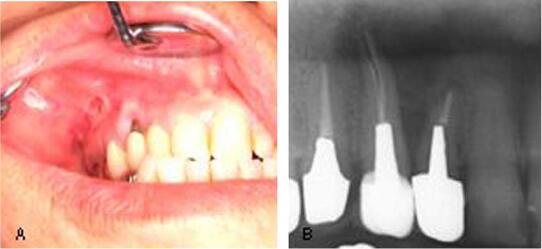

A physical examination revealed trismus and dysphagia with diffuse swelling from the right

temporal region to the precordium ( Fig.1 ).Sinceminorchestpainhadoccurred,weperformedanelec-

trocardiogram test, however, there were no abnormal findings. At the time of this examination,

she was unable to open her right eye, and crepitations were found upon palpitation of the

swelling. In the oral examination, we observed surgical wounds in the apical area on the upper

first premolar tooth on the right side ( Fig. 2 A). The dental X-ray showed the root fracture

and corresponding radiolu- cent area of the tooth ( Fig. 2 B). Based on the patient’s

explanation, the wounds seemed to be from a laser radiation trace. There were no abnormal